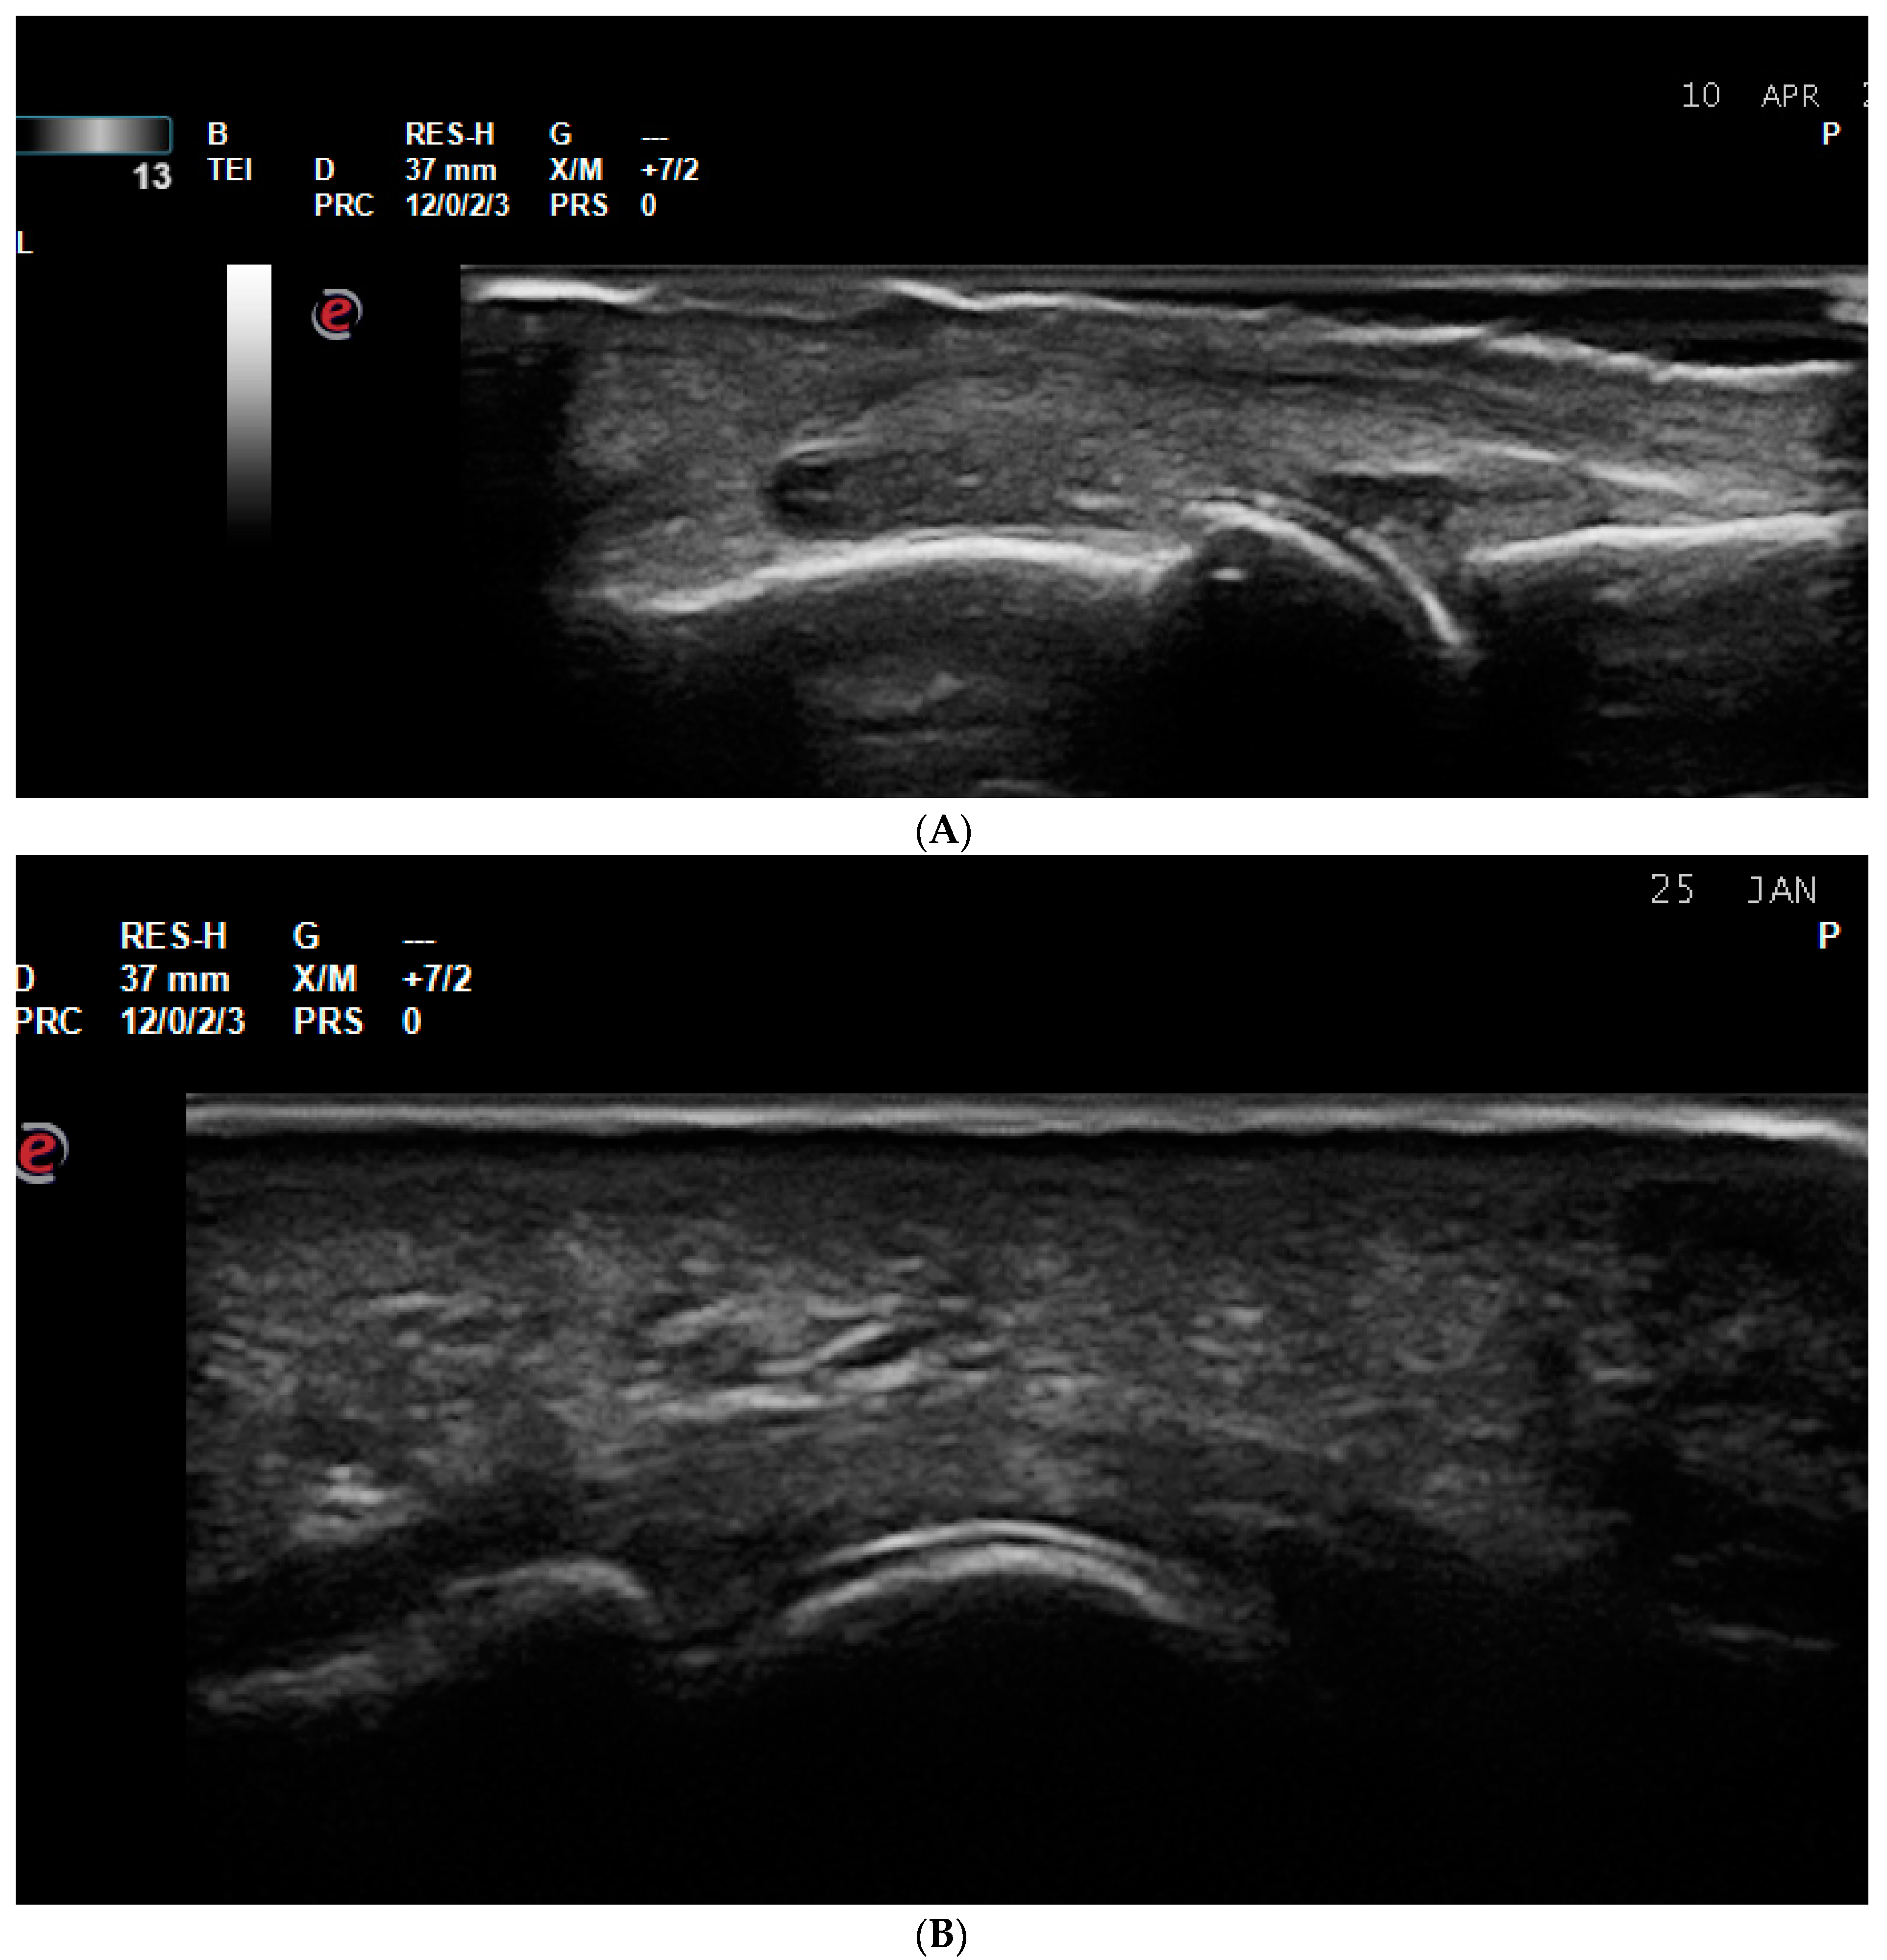

5.1. Polymyalgia Rheumatica (PMR)